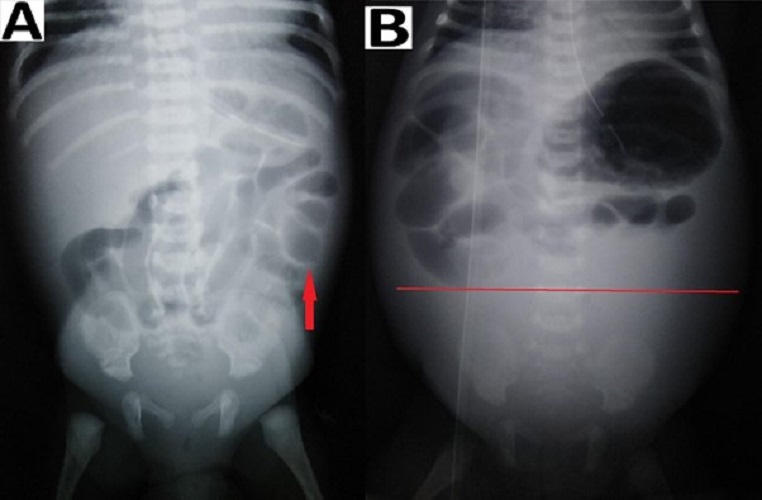

Figure 3

Preoperative radiographs showing: (A) dilated bowel loops (red arrow) at the left upper abdomen and (B) fixed dilated bowel loops (red arrow) at an interval of 24 hours.